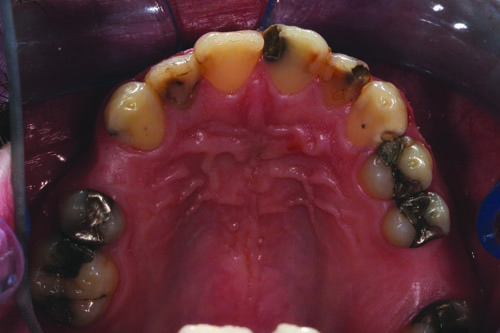

Fig. 7: Palatal view of the maxillary arch revealing the distal/lingual (DL) composite restorations on teeth #9 and #11.

Fig. 8: Occlusal view of the patient’s mandibular arch. Tooth #22 presented with a DL carious lesion without PAP, while tooth #28 presented with MOD decay without PAP.